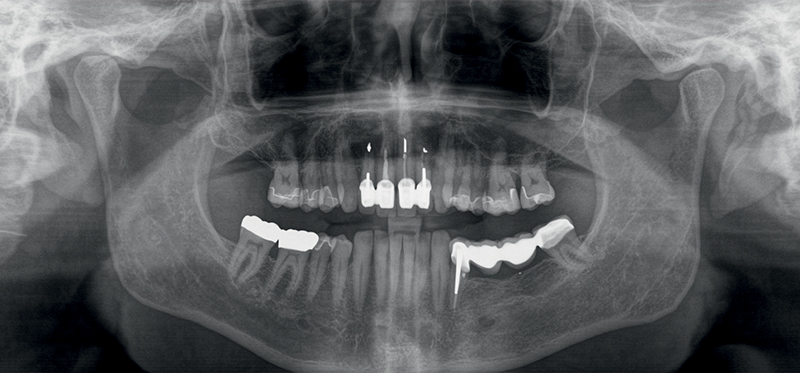

Caso 4: Una paziente, fumatrice, con parodontite avanzata e numerose cisti periapicali in entrambe le regioni superiori posteriori, presentava perimplantite terminale a carico degli impianti in titanio pre-esistenti, grave mobilità dei denti e marcata perdita ossea in tutte le regioni del mascellare. Inoltre, si osservava uno spostamento della linea mediana di ca. 4 mm, con denti mancanti (12 e 22). La maggior parte dell'osso alveolare buccale dei denti 11 e 21 era già andata perduta, e la linea del sorriso alta del paziente presentava sfide estetiche. Per compensare lo spostamento della linea mediana e creare una dentatura regolare da 16-26, la paziente optava per il posizionamento immediato di impianti a carico immediato (attraverso riabilitazione con protesi provvisoria a lungo termine), per un totale di 10 fixtures nell'arcata superiore. Gli impianti venivano attentamente monitorati, così come le condizioni parodontali della paziente. Dopo 6 mesi gli impianti venivano finalmente preparati e dotati di corone in ceramica definitive. Nello stesso periodo la paziente acconsentiva anche all’inserimento di un impianto nella regione dei molari inferiori, che portava ad una completa riabilitazione orale. Subito dopo il primo intervento chirurgico (rimozione di tutti i denti infiammati e degli impianti in titanio nel mascellare superiore, ed inserimento immediato di 10 impianti in ceramica a carico immediato), lo stato di salute generale del paziente migliorava notevolmente, come chiaramente veniva confermato 7 anni dopo (Fig. 18-21).

Fig. 19 (caso 4) - Radiografia e CBCT che mostrano difetto e perdita di struttura ossea

Fig. 20 (caso 4) - Immagine di controllo radiografica a 12 mesi dall'inserimento degli impianti